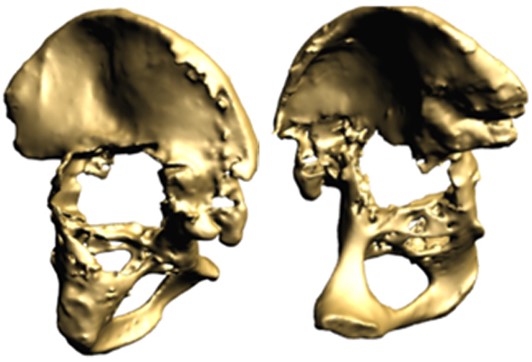

The patient, a 49-year-old woman, underwent metal-on-metal (MoM) hip resurfacing procedure in 2001 due to a unilateral hip dysplasia (DDH). 17 years later, she presented with mild hip pain but extensive loss of bone in the pelvis which was presumably caused by an inflammatory reaction to metal wear debris. Her blood metal ion levels were 100 times higher (cobalt 188 bbp and chromium 126 bbp) than from patients with well-functioning MoM hips.

The case posed multiple challenges. The patient was at imminent risk of pelvic fracture without surgery. However, surgery itself also risked fracture of the pelvis during implant removal. Furthermore, the remaining pelvic bone was poisoned by metal debris and thus the patient’s bone integrity was compromised, which could affect the stability of a new implant.

A multidisciplinary team decided that revision surgery was necessary due to the risk of fracture and very high metal ion levels. The plan involved removing the existing MoM implant and fitting a custom 3D-printed acetabular cup. The procedure required meticulous care to avoid causing fractures during implant removal. The new cup would only be effective if the pelvis remained intact.

The operation was successful, with minimal bone loss during implant removal. A custom-made titanium acetabular cup was fitted and stabilized with screws. Postoperative imaging confirmed correct implant positioning and satisfactory fixation. The patient’s recovery was positive, with significant reductions in metal ion levels and the restoration of pain-free hip function.

This case represents ALTR with MoM, which was characterized by extensive osteolysis of pelvic bone, which was presumably caused by metal wear debris. Elevated blood levels of chromium and cobalt further supported this hypothesis.

This case demonstrates the importance of precise surgical planning and execution in complex hip revision surgeries. The use of 3D-printed implants tailored to the patient's anatomy greatly improved the chances of successful fixation despite significant bone loss. Update at 6 years post operative is that the patient living a full and active life with excellent hip function. More details about this type of surgery has been published by Professor Hart: